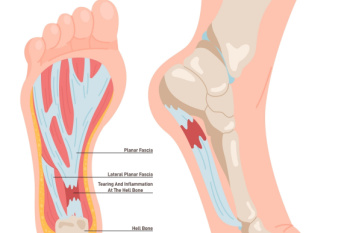

Key Insights Into Foot Pain From Plantar Fasciitis

Plantar fasciitis, a common foot ailment, affects millions of individuals worldwide, causing discomfort and hindering mobility. This condition occurs when the plantar fascia, a thick band of tissue connecting the heel bone to the toes, becomes inflamed or strained. It is characterized by sharp pain at the bottom of the foot, particularly near the heel, especially noticeable during the first steps in the morning or after prolonged periods of rest. While the exact cause remains elusive, factors such as overuse, improper footwear, high-impact activities, and tight calf muscles contribute to its onset. Plantar fasciitis is prevalent among athletes, runners, and individuals who spend extended periods on their feet. Fortunately, conservative treatments like rest, stretching exercises, and orthotic inserts, can alleviate symptoms and promote healing in many cases. However, persistent cases may require medical intervention, including corticosteroid injections or surgical procedures. If you have heel pain, it is suggested that you confer with a podiatrist who can accurately diagnose and treat plantar fasciitis.

What Is Plantar Fasciitis?

Plantar fasciitis is the inflammation of the thick band of tissue that runs along the bottom of your foot, known as the plantar fascia, and causes mild to severe heel pain.

What Causes Plantar Fasciitis?

- Excessive running

- Non-supportive shoes

- Overpronation

- Repeated stretching and tearing of the plantar fascia

The plantar fascia is a connective tissue in the heel that stretches across the bottom length of your foot. Plantar fasciitis occurs when the connective tissue becomes inflamed, causing heel pain and discomfort during physical activity. Although the condition is completely treatable, traditional methods can take up to a year to start becoming effective.

Plantar fasciitis is caused by a number of everyday activities, so understanding the condition is important for managing and treating it. One of the most common causes of plantar fasciitis is excessive running, especially with improper fitting or non-supportive shoes. Too much exercise can lead to the plantar fascia being overworked and overstretched, which can cause tears in the tissue. Along with improper fitting shoes, pronation, the rolling of the feet inward, is a common cause of plantar fasciitis. If not treated properly, the plantar fascia becomes overstretched and starts to tear, causing inflammation.

No matter what the case may be, consulting your podiatrist is the first and best step to recovery. Even the slightest amount of heel pain could be the first stage of plantar fasciitis. Untreated symptoms can lead to the tearing and overstretching of tissue. Because the tearing of tissue can be compounded if it remains ignored, it can evolve into a severe case. The solution is early detection and early treatment. Talk to your podiatrist about the possibilities of plantar fasciitis if you’re experiencing heel pain.